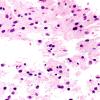

Astrocytoma, IDH-mutant, WHO Grade 2 (8)